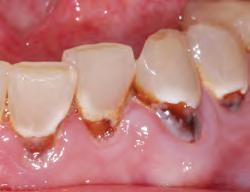

MICROLEAKAGE

PROVISIONAL REMOVED STAINING

2. Upon removing some of the composite, the extent of leakage is more evident. Contamination has occurred, therefore compromising the seal. Hemostatic, blood, sulcular fluid, saliva, and byproducts from anerobic bacteria can be sources of contamination. Retreatment is necessary.